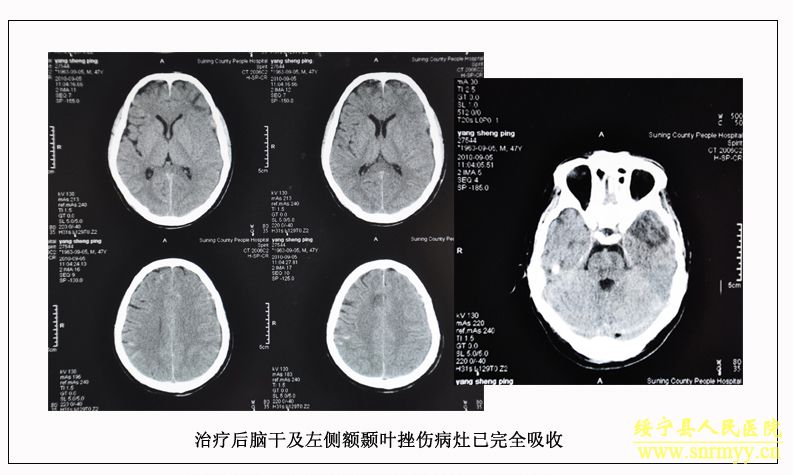

危急时刻,分管副院长沈建辉当即通知外二科、手术室医师全力做好抢救准备,并针对病人伤情讨论了救治方案,统一意见后,立即将病人送入手术室进行缝合、止血、气管切开等一整套手术,同时积极用药以降低颅内压、颅内出血、抗感染防治并发症、保护脑神经等对症支持治疗。在外二科全体医护人员的精心治疗和护理下,同死神搏斗的病人终于闯过了道道难关,脑水肿危象度过了,肺部感染控制住了。二十天后(9月14日),病人终于睁开了眼睛。

经再次检查,病人的身体状况明显好转,但意识模糊。9月28日,病人意识逐渐清楚。为方便护理,让病人早日康复,由沈建辉副院长亲自主刀,刘兴淼医师为助手,为病人实施了左股骨开放复位和交锁髓钉内固定术。10月21日,病人生活基本能自理,近日即可出院。 (2010.10.26)